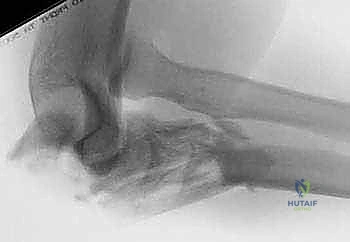

TECH FIG 1 • A. A lateral radiograph with the arm in plaster shows a transverse, noncomminuted fracture of the olecranon. B. An open reduction is held with a fracture reduction forceps.

TECH FIG 1 • A. A lateral radiograph with the arm in plaster shows a transverse, noncomminuted fracture of the olecranon. B. An open reduction is held with a fracture reduction forceps. (continued)